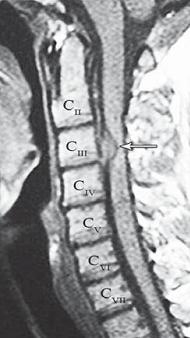

МРТ № 20

На МРТ № 19 наблюдается дорсальная грыжа межпозвонкового диска шейного отдела позвоночника в сегменте СV-СVI с компрессией спинного мозга

Замечу, что если грыжа межпозвонкового диска имеет достаточно большой размер и локализована в шейном отделе, то она способна вызвать не только соматические нарушения, но и даже психические расстройства. Причина кроется в сдавлении дурального мешка грыжей межпозвонкового диска (дуральный мешок — это герметичный соединительнотканный мешок, формируемый твёрдой мозговой оболочкой, в котором расположен спинной мозг). Как известно, спинной мозг не имеет болевых рецепторов. Однако вышеуказанная патология приводит к локальному устойчивому возбуждению определённых зон коры головного мозга. На субъективном уровне это может проявляться как постоянное чувство тревоги (так называемый «синдром ожидания»).